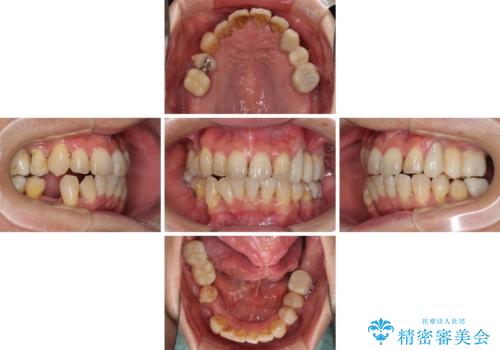

- 歯並びやグラグラする奥歯など、気になる所を全部治したいとのことで来院された患者様です。

奥歯は咬み合わせや歯周病により歯槽骨が失われていたり、むし歯や破折している歯などがあったりと、歯周病治療やインプラント補綴、矯正治療など、総合的に治療が必要と診断されました。

まずは歯周病治療やインプラント埋入を行い、環境が整った後にワイヤーを併用したインビザライン矯正を行い、オールセラミッククラウンにて補綴治療を行うこととしました。

初診時に4年かかりますとお伝えし、実際に4年数ヶ月を要する治療となりました。

治療中は仮歯が頻繁に脱落したり、歯周外科によりむき出しとなった歯根が知覚過敏を起こしたりと、苦労は絶えませんでしたが、4年の治療の後にスッキリと仕上げることができました。